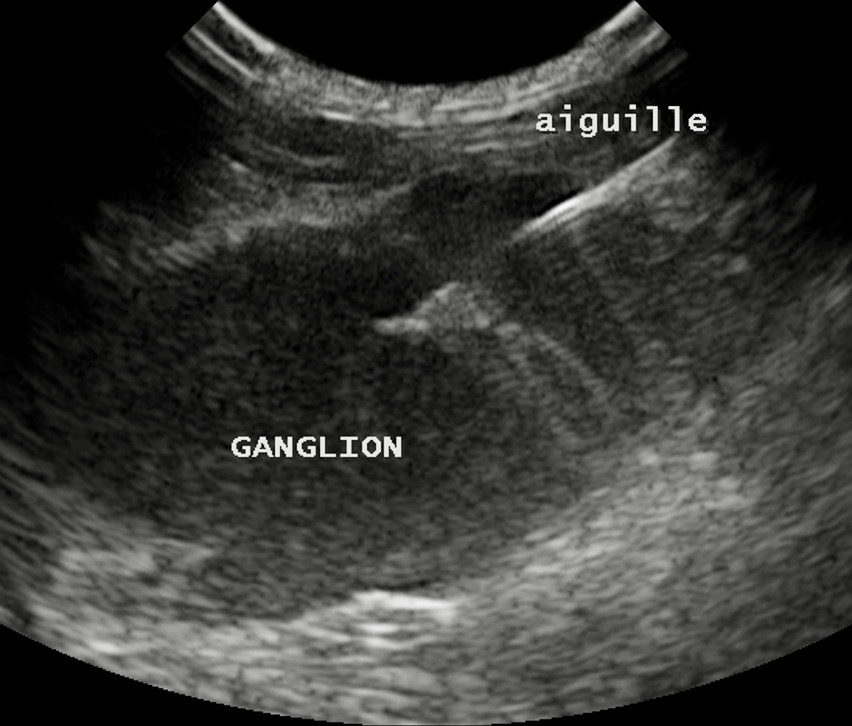

Pour progresser dans un diagnostic de PIF, l’échographie est nettement plus intéressante : côté abdomen surtout, elle permettra non seulement de confirmer (ou pas) la présence de liquide, même lorsque celui-ci est en faible quantité. Elle permettra aussi de voir, à travers ce liquide, l’aspect des organes abdominaux, et notamment les modifications dont on a parlé plus haut : hypertrophie des ganglions, déformations de la paroi intestinale, augmentation ou diminution de la taille des reins avec un éventuel anneau médullaire (on en a vu un exemple dans la partie « Symptômes »), modifications de la forme ou de la structure du foie, etc. Elle permettra enfin de réaliser des ponctions : en premier lieu pour aspirer du liquide d’ascite, (quand il y en a beaucoup, à la limite, on pourrait se passer d’échographie, mais quand il y en a peu, l’écho est indispensable), mais aussi pour ponctionner des organes suspects en vue d’analyses.

L’examen cytologique présente l’avantage de la simplicité (une ponction à l’aiguille, et un examen au microscope dans la foulée, après étalement et coloration), mais ne donne pas un diagnostic de certitude. Il permet malgré tout de se rendre compte si les cellules collectées sont compatibles avec l’hypothèse de PIF (réaction pyogranulomateuse au milieu des cellules normales de l’organe ponctionné), et d’éliminer d’autres hypothèses (par exemple, un lymphome… surtout si c’est un gros ganglion que l’on a ponctionné). Les publications semblent montrer que ça marche bien pour les cytoponctions de ganglions, (Green, 2023), un peu moins bien pour les cytoponctions de foie, et encore moins pour celles de rate.

Photo de gauche : ponction du très gros ganglion mésentérique présenté plus haut : l’aiguille, en place dans le ganglion pour le prélèvement, est bien visible. Photo de droite : examen microscopique de ce prélèvement, après étalement et coloration : la population cellulaire est variée, ce qui exlut un envahissement tumoral (en particulier un lymphome). Au milieu des cellules ganglionnaires, on observe des polynucléaires neutrophiles et des macrophages, (celui au centre de la photo a avalé un PNN), compatibles notamment avec une PIF. Une PCR réalisée sur le même prélèvement a confirmé le diagnostic de PIF, avec une très forte charge en coronavirus.

Outre les fluides, il est également intéressant de réaliser une RT-PCR sur un prélèvement obtenu par cytoponction (aspiration dans un ganglion mésentérique, par exemple). En revanche, rechercher du FCoV par RT-PCR dans les selles ne présente vraiment aucun intérêt, puisque plein de chats qui vont très bien ont du FCoV non muté dans l'intestin ; le seul intérêt éventuel serait de déterminer lesquels, parmi les 15 chats en bonne santé qui squattent ma chambre et mon salon, excrètent du coronavirus intestinal, (sachant, on l'a vu, que l'excrétion peut être intermittente !), afin de savoir où j'en suis, et comment gérer la situation. Bof… On en reparle plus loin, dans la partie "Prévention". En tout cas, définitivement aucun intérêt pour le diagnostic de la PIF.